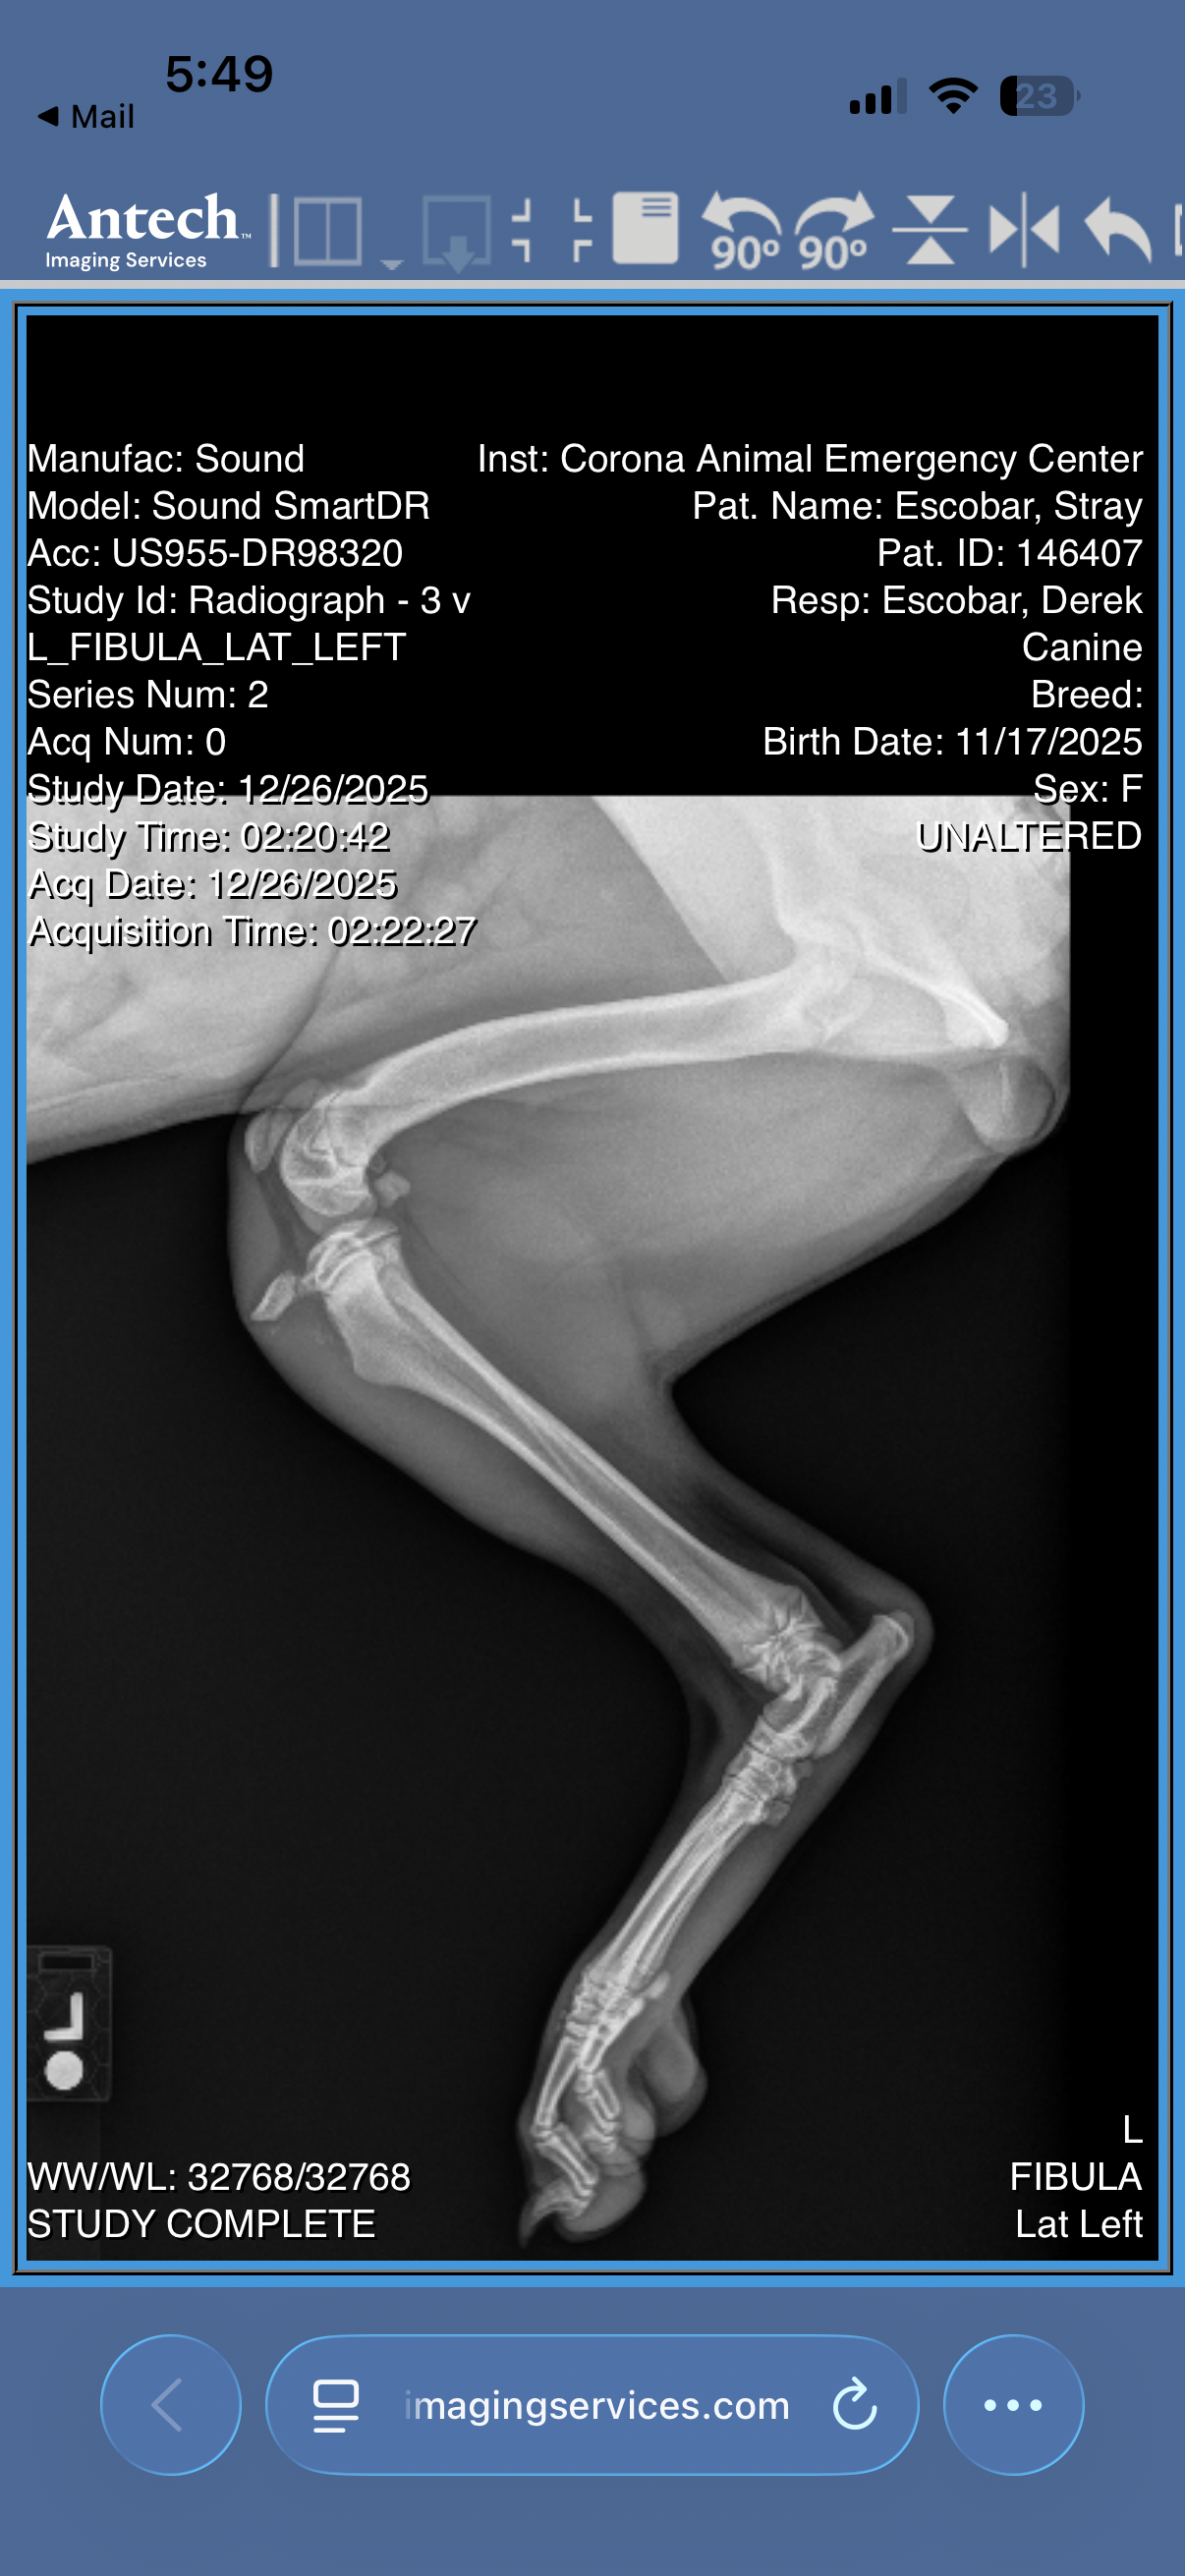

I rushed her to a 24-hour vet, and after eight long hours and $1,100 later, we learned that this sweet girl has a fractured left hind leg. The vet explained that her injury is severe, and splinting isn’t an option.